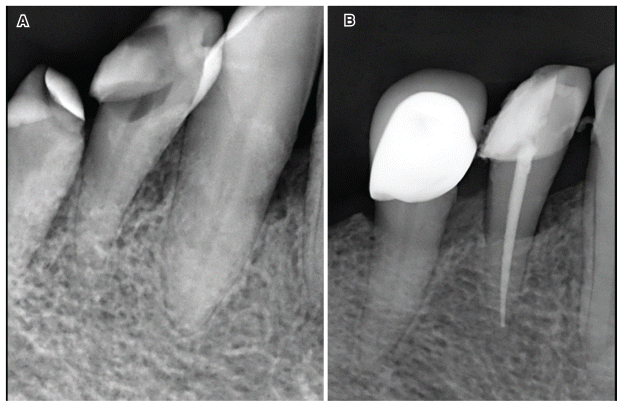

Data were recorded in Excel and analyzed statistically using chi-square tests and multinomial logistic regression. An example of clinical treatments in multi-rooted and single-rooted cases performed in the present study is shown in Figures 1 and 2.